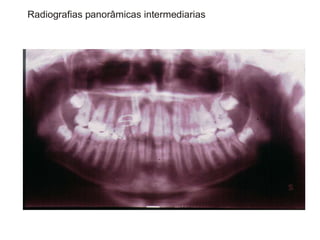

TRANSPOSIÇÃO TOTAL - CANINO COM INCISIVO LATERAL MANOBRAS PARA CORREÇÃO DA ROTA DE ERUPÇÃO